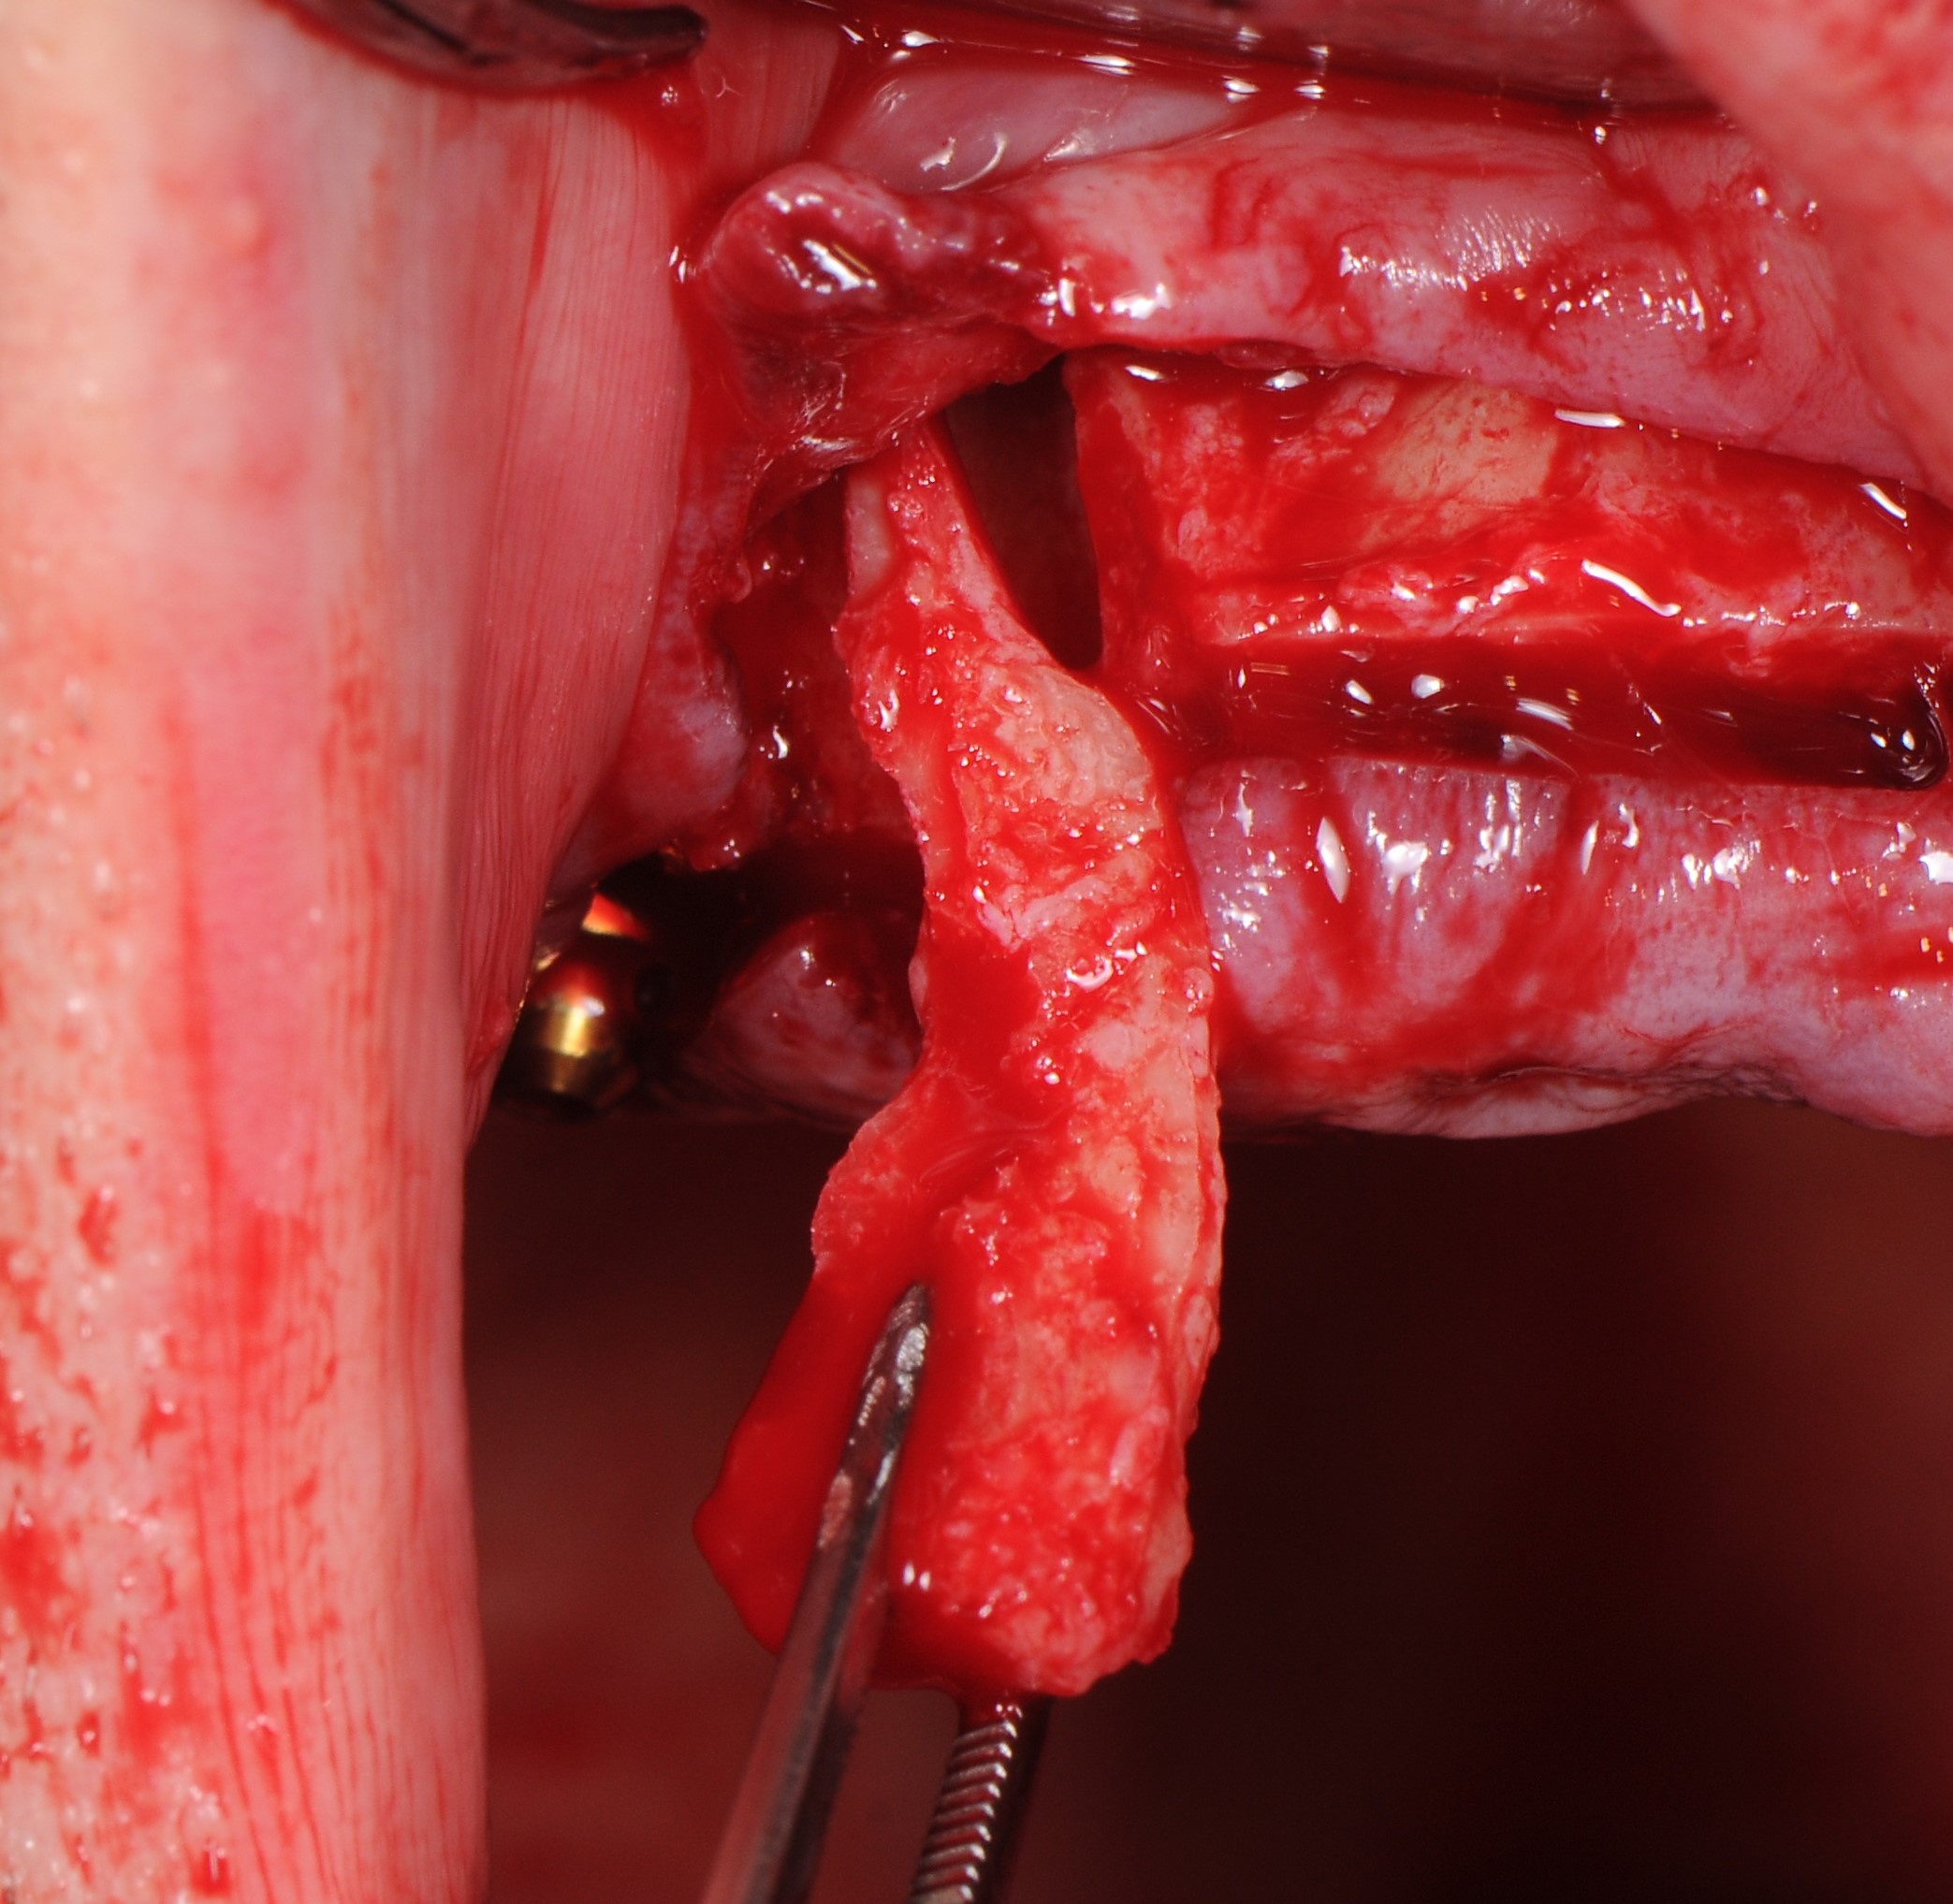

После скелетирование слизисто-надкостничного лоскута удален зуб 1.3 . Во фронтальном отделе дисковой пилой проведена редукция альвеолярного гребня верхней челюсти сохранением костного фрагмента. (рис 11,12,13)